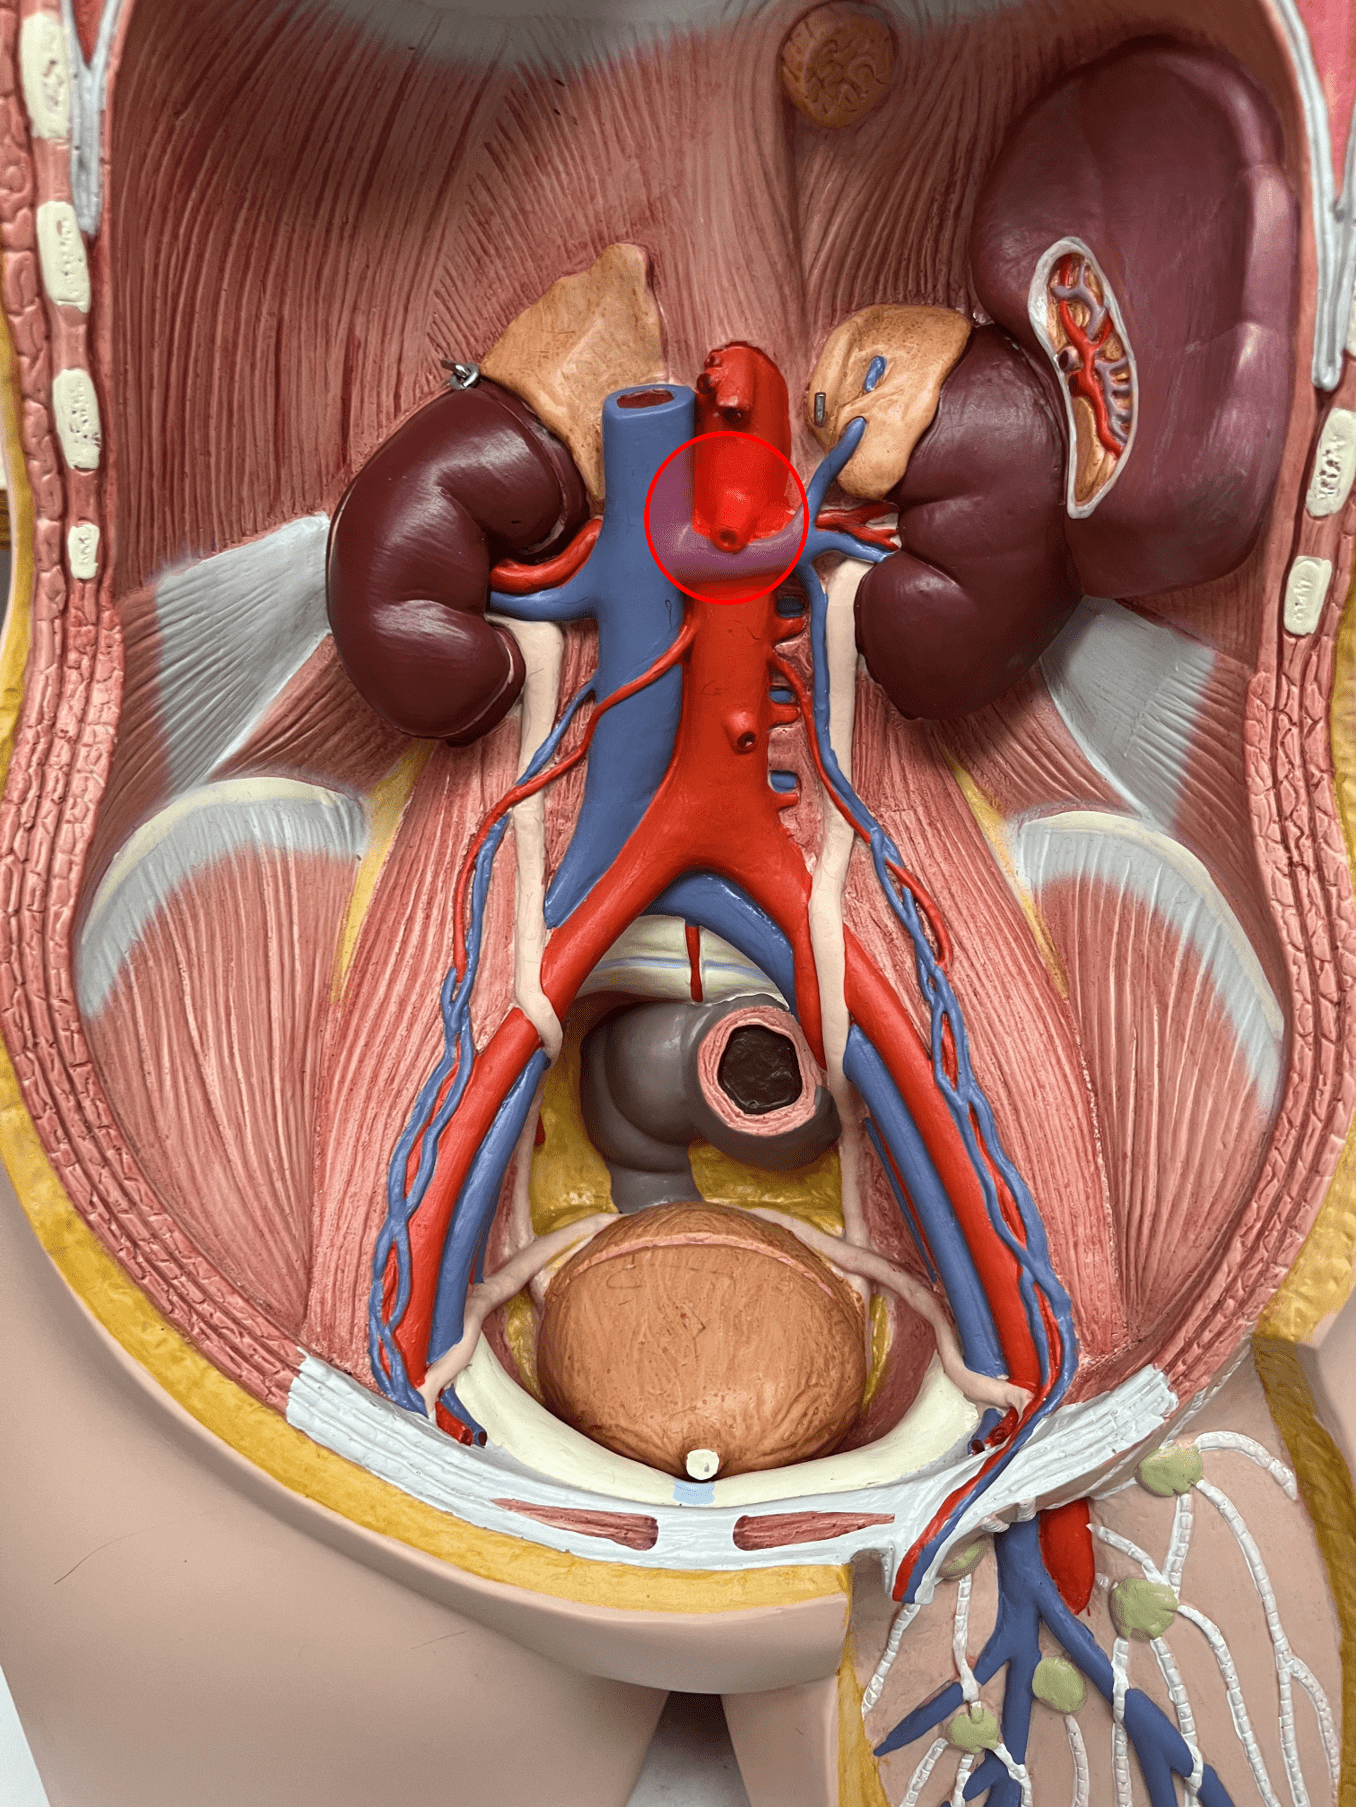

7

tunica media